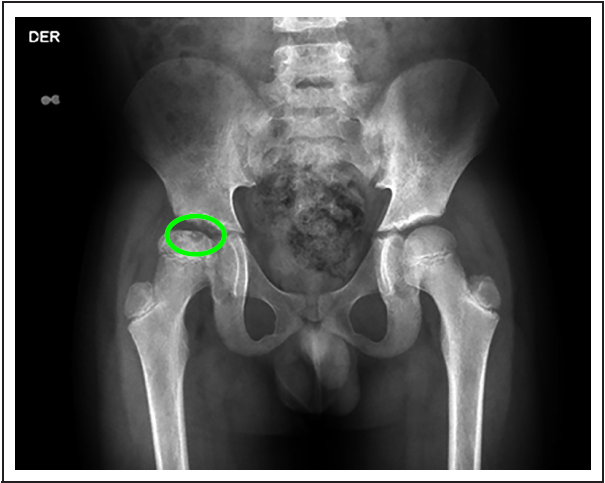

A los 9 años, en cita de control, menciona tener 15 días de evolución de claudicación a la marcha y dolor en cadera derecha, al examen físico se encuentra limitación funcional y dolor a la exploración, y por radiografías convencionales de cadera se evidencia necrosis del 30 % de la cabeza del fémur (figura 1). Ortopedia considera que no requiere manejo quirúrgico en ese momento y se le da manejo conservador. El manejo inicial se da con analgesia con ibuprofeno y transfusión de glóbulos rojos empacados. En radiografía de control 5 meses después ya se encuentra en etapa de remodelación. (figura 2)